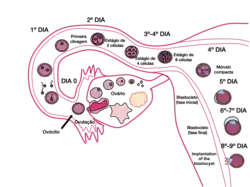

Fecundação e implantação nos seres humanos

Nos seres humanos, a embriogénese, ou período embrionário, tem início com a fecundação e prolonga-se até ao início do período fetal. Após a fecundação, o zigoto desloca-se lentamente ao longo da trompa de Falópio em direção ao útero. Ao longo desta viagem de mais de uma semana, o zigoto divide-se em células idênticas. Esta divisão celular tem início aproximadamente entre 24 a 36 horas após a fecundação. Ao fim do 4º dia de divisão celular, o zigoto dá origem a uma esfera sólida de 16 ou 32 células denominada mórula. Ao chegar ao útero, cinco dias após a fecundação, esta esfera apresenta-se oca e tem entre 50 e 100 células. Nesta fase passa a ser denominada blastócito, demorando cerca de seis dias até nidificar na parede uterina. O revestimento de proteínas do blastócito dissolve-se, o que permite às suas células trofoblásticas entrar em contacto e aderir às células endometriais da parede uterina. O embrião une-se com o endométrio através de um processo denominado nidação, que ocorre oito a dez dias após a ovulação. Após alguns dias, forma-se o celoma extra-embrionário que se tornará na cavidade coriónica, a qual irá conter o embrião, o líquido amniótico e o cordão umbilical. Desenvolve-se também a cavidade amniótica entre o citotrofoblasto e a massa de células interna. Desenvolve-se também a placa pré-cordal, que indica o futuro local da boca e da região cranial. Nesta fase, o embrião cresce rapidamente e começam a tomar forma as principais características externas. Este processo, denominado diferenciação celular, produz os diferentes tipos de células do organismo.[41][42][43]